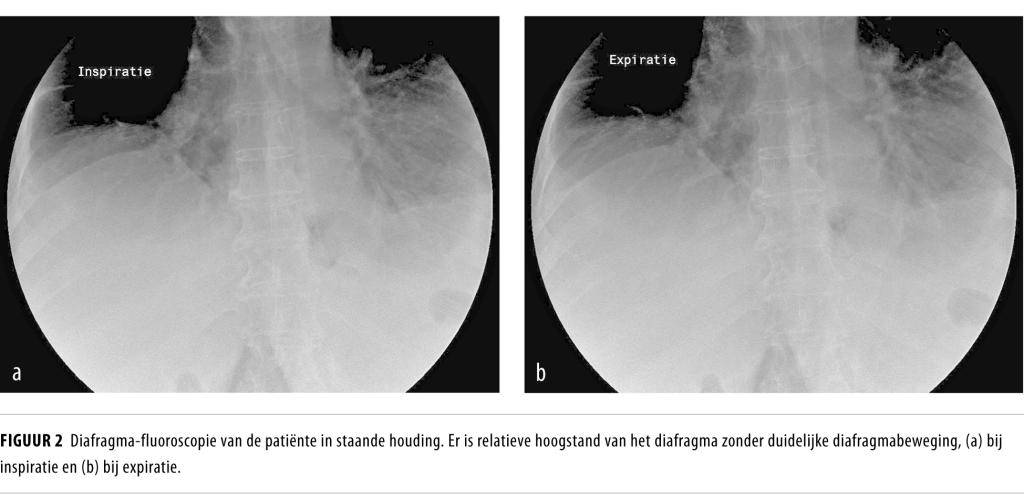

Wij zagen een 67-jarige vrouw wegens plotse orthopneu. Beeldvormend onderzoek toonde bilaterale diafragmaparalyse en emg bevestigde neuropathie van beide Nn. phrenici. De diagnose luidde ‘bilaterale neuralgische amyotrofie’. Patiënte kreeg nachtelijke ondersteuning van de ademhaling in de vorm van zuurstoftherapie met hoge nasale flow. Deze symptomatische behandeling had een goed effect.

Neuralgische amyotrofie wordt gekenmerkt door pijn in de nek of schouderregio, gevolgd door zowel motorische als sensorische neuropathie van de plexus brachialis. De incidentie wordt geschat op 1 op de 1000 per jaar. Bij een zeldzame variant van dit ziektebeeld zijn beide Nn. phrenici aangedaan, waardoor diafragmaparalyse en ernstige orthopneu ontstaan.